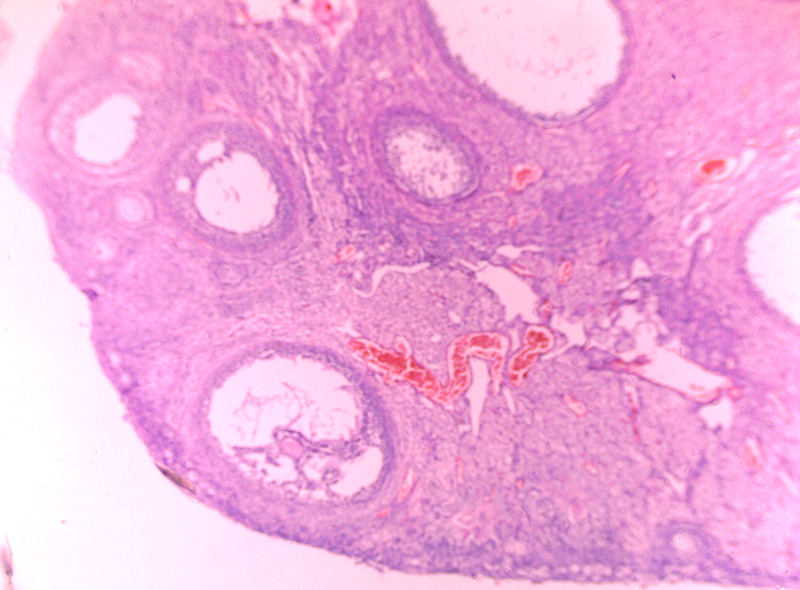

成熟卵巢兔